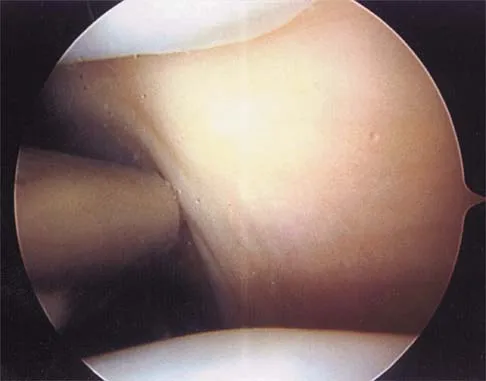

Question 84

Figure 19 shows an arthroscopic view from the anterior lateral portal of the knee looking into the suprapatella pouch. The use of an electrothermal device during this procedure most commonly causes significant postoperative complications by damaging which of the following structures?

Explanation